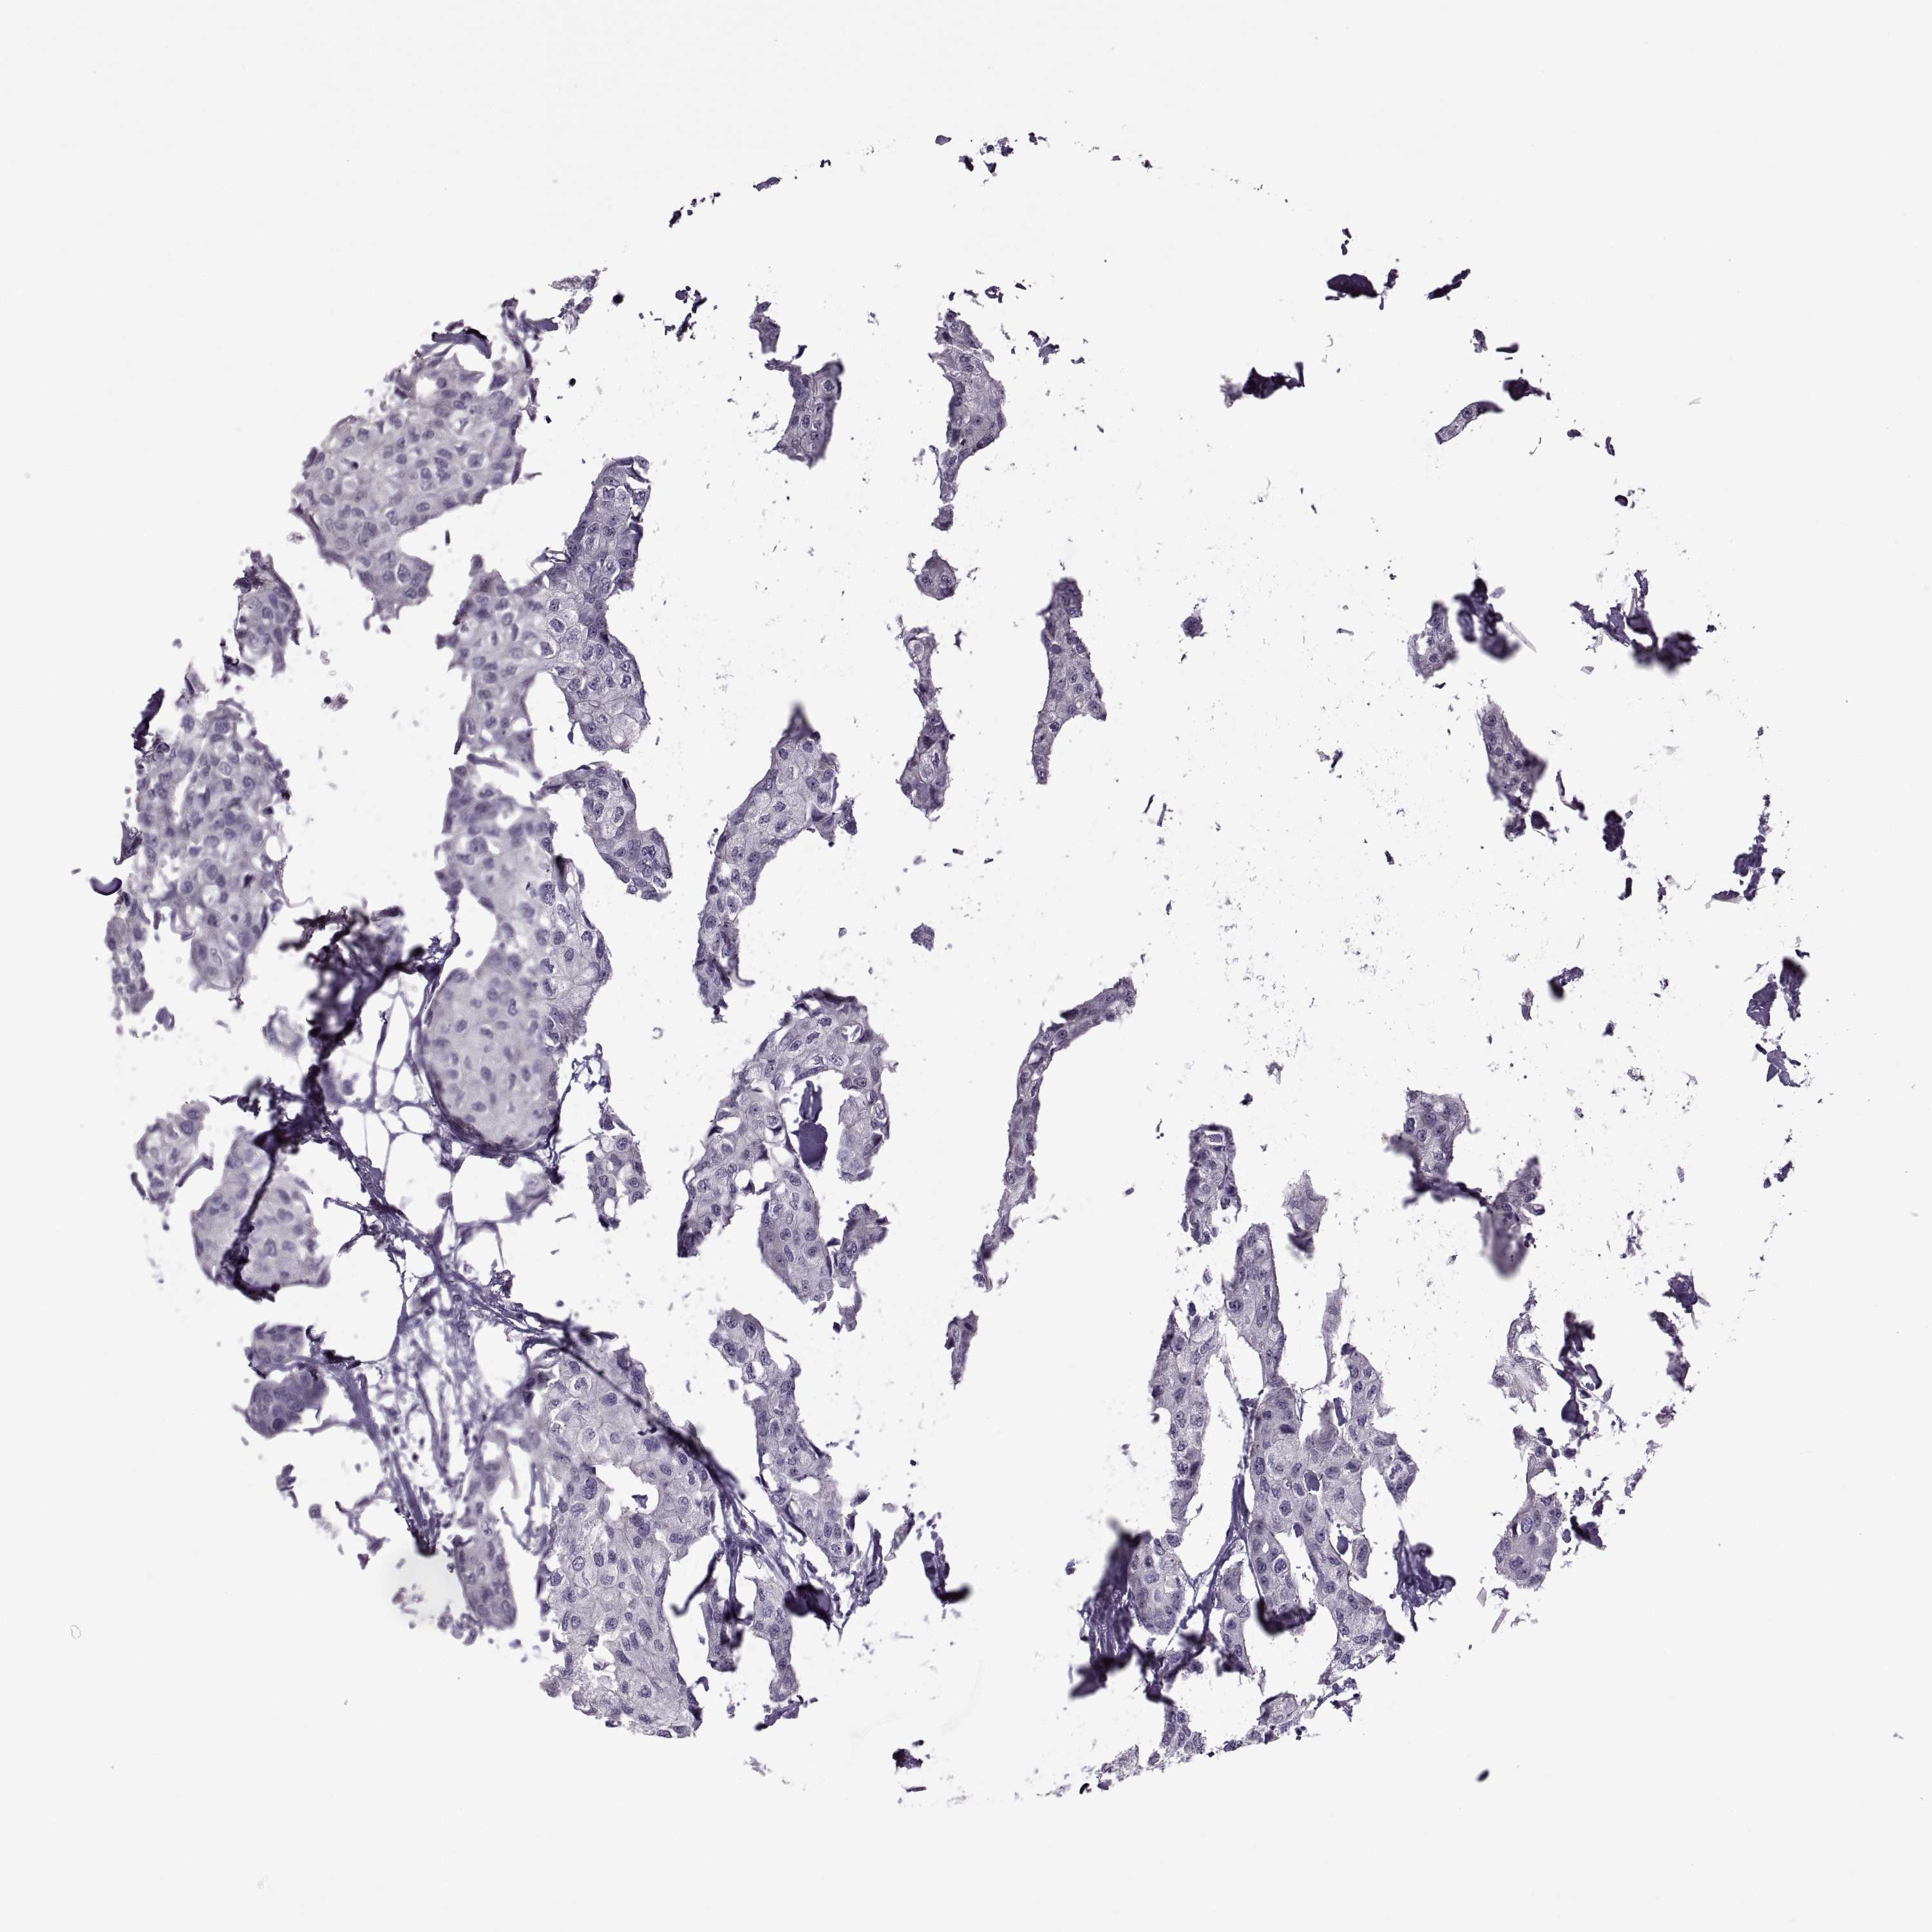

CANCER BREAST CANCER Show tissue menu

BRCA TCGA BRCA VALIDATION PROTEIN EXPRESSION

Breast cancer

Human cancer